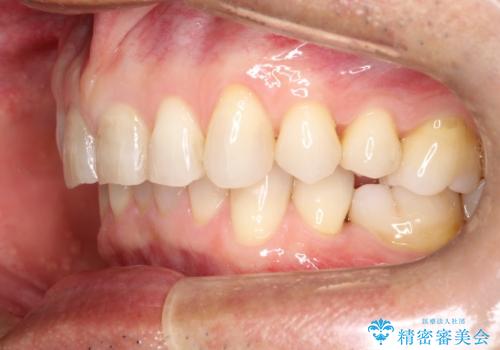

上の前歯の隙間とがたつきをインビザラインできれいな歯並びへ

- 以前矯正治療を他院にて行っており、最近上顎の隙間とガタガタが気になるとのことで来院されました。

上顎のみインビザラインにて矯正治療を行うこととなりました。

使用時間を守っていただけたので、比較的スムーズに矯正を終了することができました。